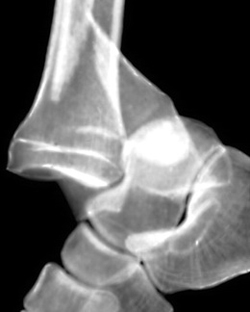

Диагноз устанавливают на основе рентгенограмм в профильной и фасной проекциях. Чтобы избежать ишемических осложнений, диагноз «подтаранный вывих стопы» требует от врача оказания неотложной травматологической помощи. Эта помощь должна учитывать конкретные варианты повреждений подтаранного сустава.

Подтаранный вывих стопы встречается крайне редко. Он возникает при резком подворачивании стопы и сопровождается разрывом связок, сильной болью, отеком и деформацией. Для уточнения диагноза и исключения переломов проводят рентгенографию.